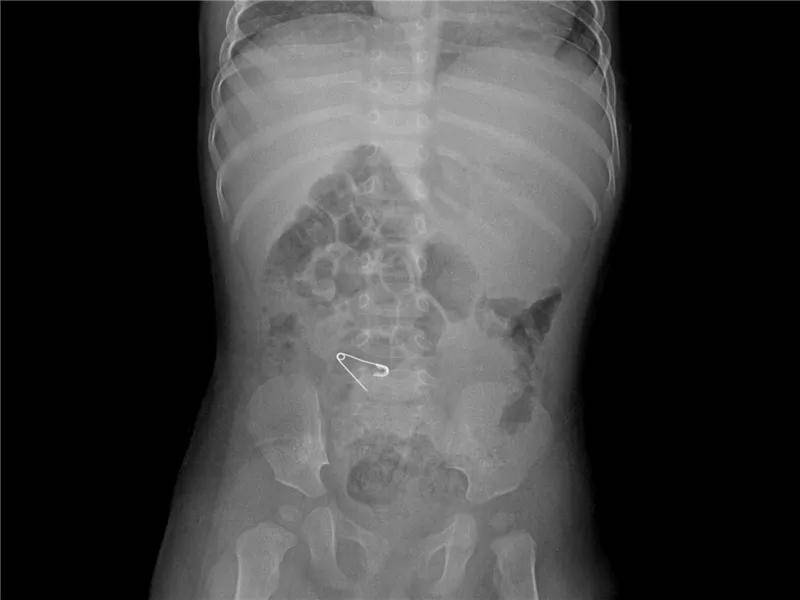

1岁·别针

前一日中午12时左右误服“别针”一枚。还是打开的别针,真担心会戳到哪里,太危险了!